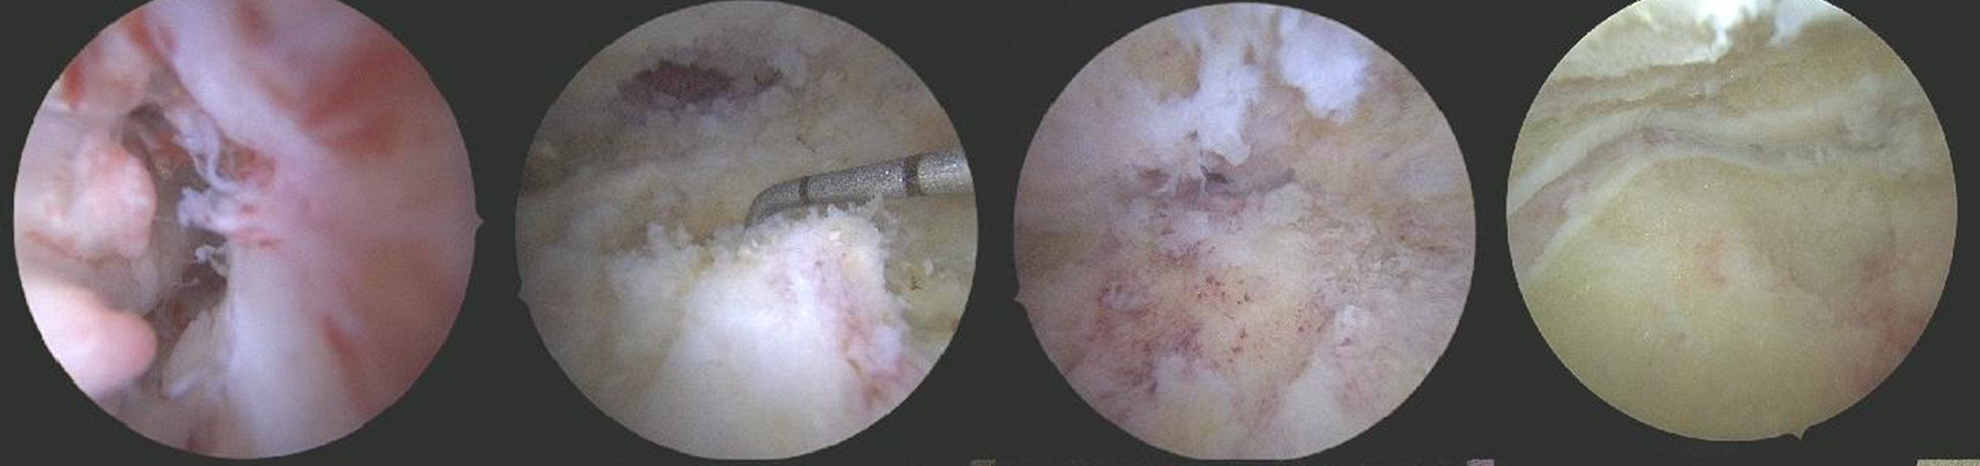

【治療中】關節鏡清創搭配自體骨移植

傳統踝關節與踝下關節融合手術,通常需要相當大的切口才能完整清理關節面;然而此病患關節腔內充滿纖維化組織與碎骨塊,若採傳統方式,傷口大、感染風險高,對糖尿病病人術後的傷口照顧更是一大挑戰。

在手術室護理師精確器械準備與流程協調下,我們採用關節鏡微創技術進行手術。手術過程中先於仰躺姿勢以前踝鏡處理踝關節,再翻成俯臥姿勢以後踝鏡處理距下關節;麻醉護理師全程嚴密監測病人生命徵象、體溫與疼痛控制,確保長時間手術的安全性。

雖然整體手術時間延長至將近7 小時,但透過關節鏡,我們得以徹底清除壞死組織,將關節面磨至出血骨面,並將原本鬆脫的內踝骨塊研碎後填入融合區作為自體骨移植,提升骨癒合成功率。這樣高度複雜且耗時的手術,仰賴骨科醫師、麻醉與手術室護理團隊的高度默契與耐心合作,才能順利完成。